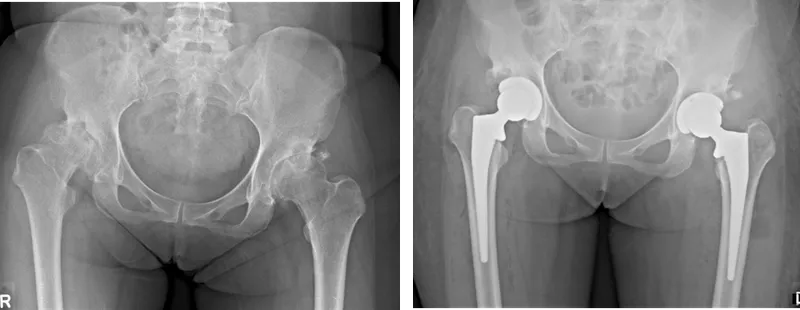

Total Hip Arthroplasty (THA) replaces a damaged hip joint with a prosthesis, aiming for pain relief & function restoration.

- Investigations: X-rays (AP Pelvis, Lat Hip), ESR/CRP (infection screen).

Components:

- Acetabular Cup: Ti/Co-Cr alloy; porous coating (uncemented).

- Liner: UHMWPE, Ceramic; locking mechanism.

- Femoral Stem: Ti/Co-Cr alloy; designs: tapered wedge, CPT (Collarless Polished Taper).

- Femoral Head: Ceramic (e.g., Biolox delta), Co-Cr; sizes: 28mm, 32mm, 36mm.

Fixation Methods:

- Cemented: Polymethylmethacrylate (PMMA). Indications: older patients, poor bone stock, irradiated bone.

- Uncemented (Press-fit): Relies on bony ingrowth. Indications: younger patients, good bone stock.